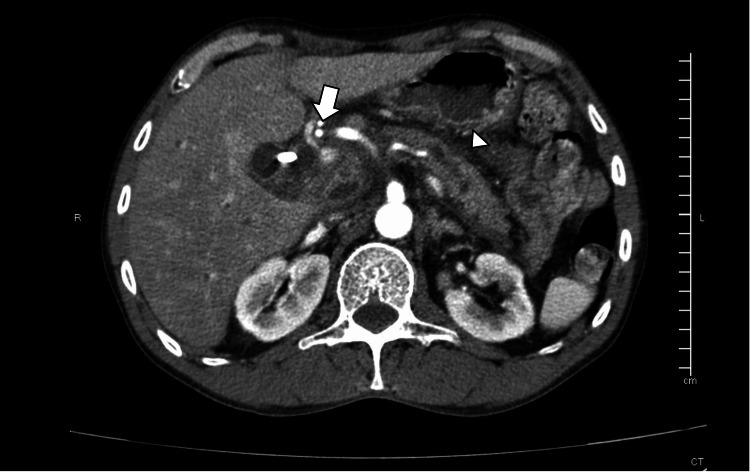

CT imaging showed biliary dilatation with an endoprosthesis and peripancreatic edema (Figure 3).